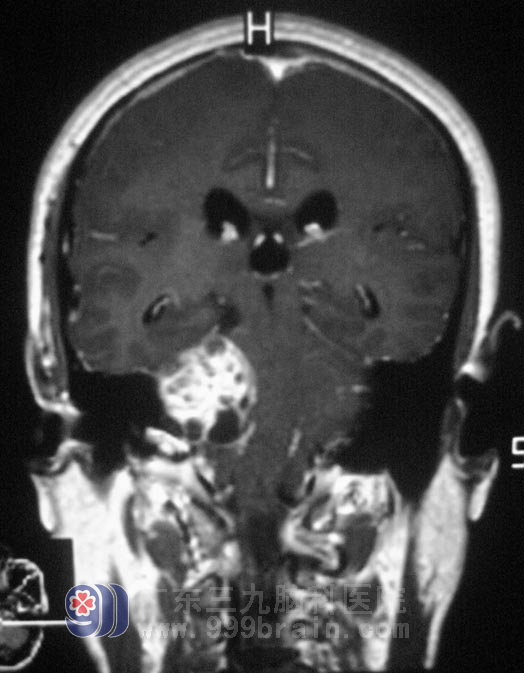

在广东三九脑科医院综合神经外科就诊,头颅MR提示:右侧桥小脑角区占位,大小53.2mm×26.1mm×49.9mm,初步考虑为听神经瘤。在五官科治疗5年无果,祸根竟然又是脑肿瘤。

10月11日,鲁明主任主刀,在显微镜下行右侧桥小脑角占位性病变切除术,术中见肿瘤边界清楚,呈囊实性,部分质韧,血供丰富,分块大部分切除肿块,小部分肿物与脑干及后组颅神经粘连紧密,经过慎重考虑行部分切除术,对后组颅神经保护完好,修补硬膜,顺利结束手术。两天后复查MR示肿瘤基本切除。术后病理结果为:(右侧桥小脑区)神经鞘瘤(听神经瘤)。